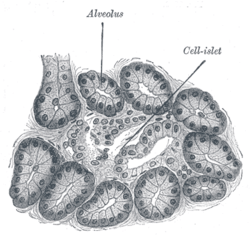

Mouse islet immunostained for glucagon Illustration of dog pancreas. 250x.

Illustration of dog pancreas. 250x.